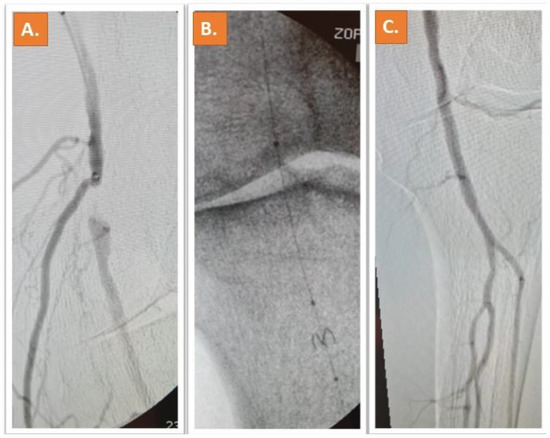

Representative Cases: Two cases of patients who underwent Jetstream and Phoenix atherectomy are shown in Figure 1 and Figure 2.

Figure 2. A calcified lesion in the P1 segment of the popliteal artery can be depicted in (A) (blue arrow), in a female 81 years old patient with lifestyle limiting claudication (RC4). After 2.4 mm deflecting Phoenix atherectomy (B), significant lumen gain is obtained (C). The result after atherectomy and DCB including the perfusion of the peripheral vessels can be appreciated in (DG) [11].